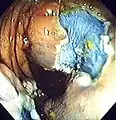

The first step is usually a digital rectal examination (DRE), to examine the tone of the anal sphincter and to determine if preparation has been adequate. A DRE is also useful in detecting anal neoplasms and the clinician may note issues with the prostate gland in men undergoing this procedure.[55] The endoscope is then passed through the anus up the rectum, the colon (sigmoid, descending, transverse and ascending colon, the cecum), and ultimately the terminal ileum. The endoscope has a movable tip and multiple channels for instrumentation, air, suction and light. The bowel is occasionally insufflated with air to maximize visibility (a procedure that gives the patient the false sensation of needing to take a bowel movement). Biopsies are frequently taken for histology. Additionally in a procedure known as chromoendoscopy, a contrast-dye (such as indigo carmine) may be sprayed through the endoscope onto the bowel wall to help visualize any abnormalities in the mucosal morphology. A Cochrane review updated in 2016 found strong evidence that chromoscopy enhances the detection of cancerous tumors in the colon and rectum.[56]

Polyp is identified.

A sterile solution is injected under the polyp to lift it away from deeper tissues.

A portion of the polyp is now removed.

The polyp is fully removed.